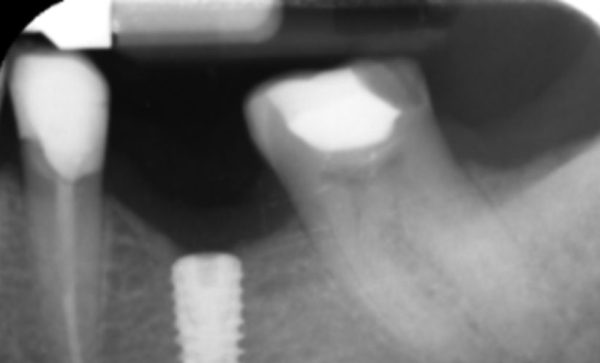

I have been a patient of Dr Verma for 8 years, my treatment has included crowns and an implant. Treatment plans and options are explained to me clearly, my concerns and anxieties are allieviated without hurry or pressure in a gentle and reassuring way. I feel my patient satisfaction is valued.

Sukal has been my dentist for many years, from simple check ups to a dental implant! I have always felt comfortable in the dentist chair and happily watched the TV on the ceiling while work is done on my teeth and never once felt any pain and always felt comfortable. I would never go anywhere else! Thank you all for being kind, caring and helpful at all times :-) Sarah Galloway